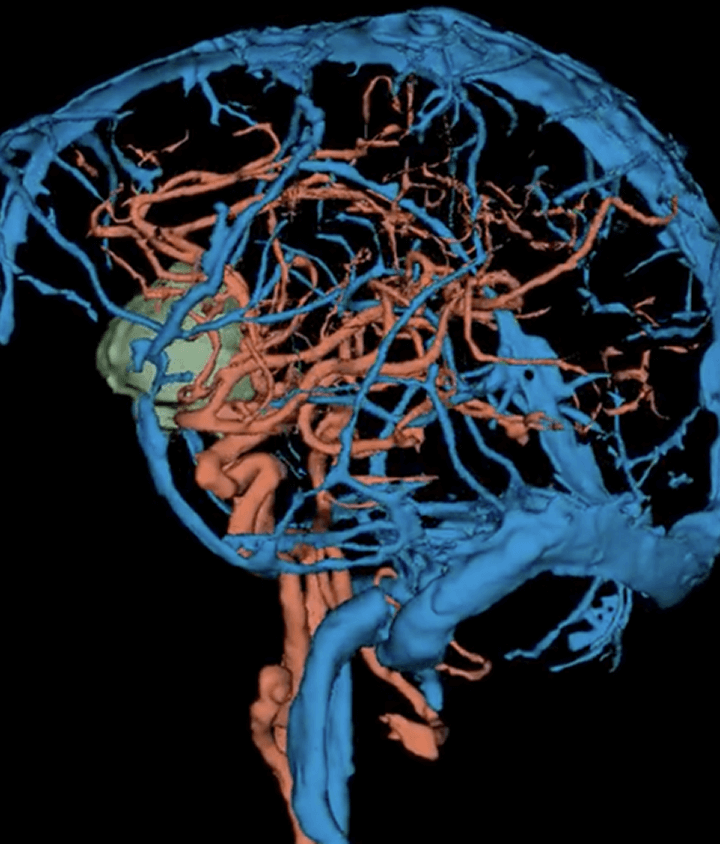

Vessel and Brain tumor segmentation

Brain Tumor: radiology labeling on 3D Slicer